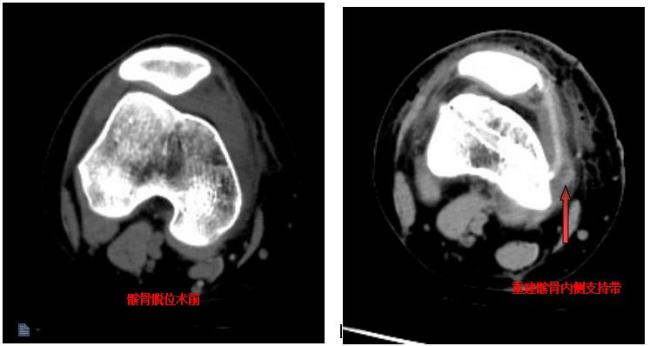

复发性髌骨脱位矫正